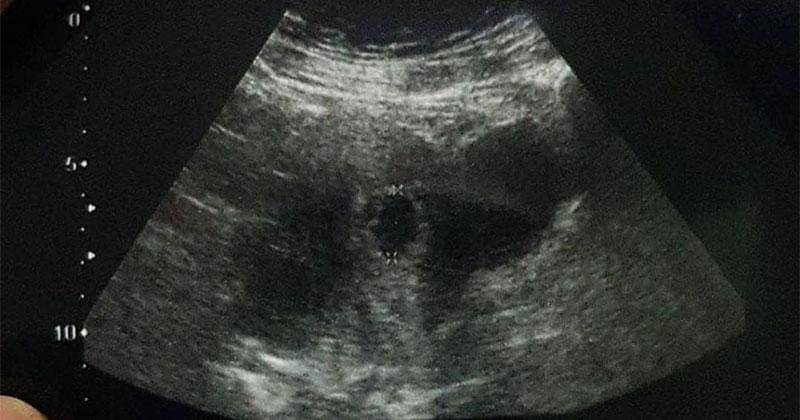

Perlu diketahui bahwa secara umum perkembangan janin pada minggu ketujuh sudah mirip ukurannya dengan biji buah apel hijau dengan panjang 1,27 cm.

Tak hanya itu, usia kehamilan yang sudah memasuki minggu ketujuh memperlihatkan banyak perkembangan jika pertumbuhannya benar-benar sehat. Berikut beberapa perkembangan secara umum pada janin di minggu ketujuh, seperti: